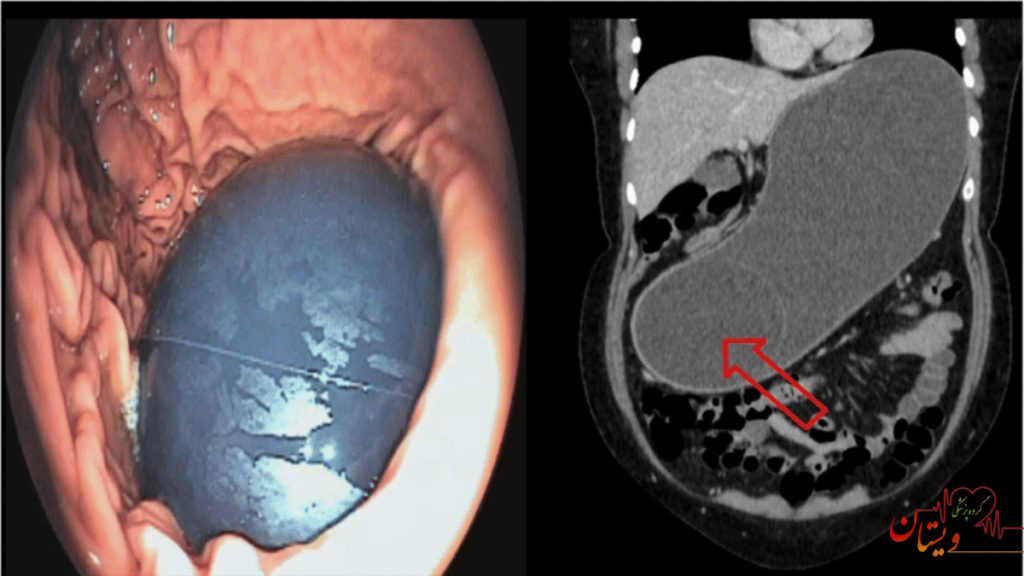

عکس بالون معده

عکسهای بالون معده معمولاً یا در حین عمل آندوسکوپی گرفته میشوند یا تصاویر اشعه ایکس و MRI بعد از قرار دادن بالون را نشان میدهند. این عکس ها نشان میدهند چگونه بالون با حجم مشخص فضای معده را اشغال کرده و احساس سیری سریع ایجاد میکند. تصاویر واقعی میتوانند بیمار را با اندازه و شکل دقیق بالون آشنا کنند.